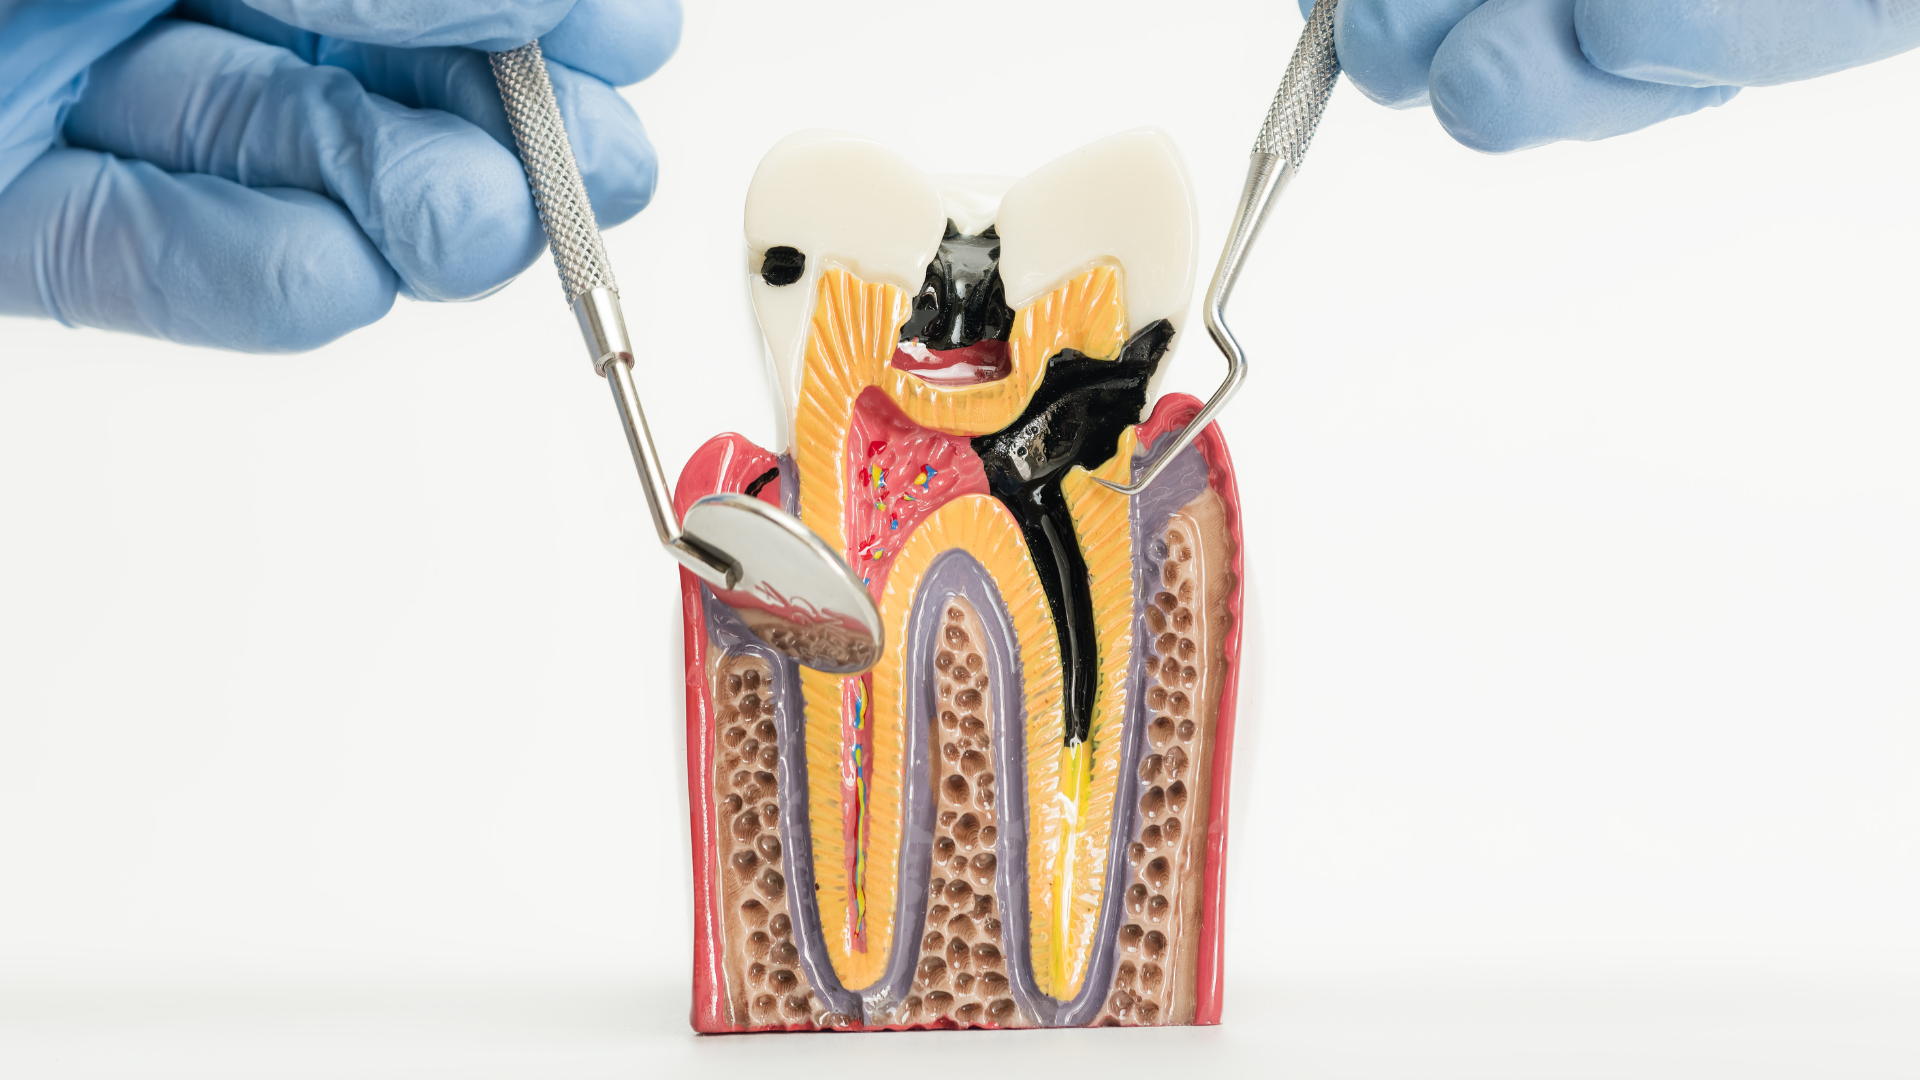

Come nasce una carie

Le carie dentali sono aree danneggiate del dente causate dall’interazione tra i batteri presenti in bocca e gli zuccheri degli alimenti consumati: questi zuccheri si trasformano in acidi in grado di deteriorare progressivamente la superficie del dente.

La carie è un processo graduale. All’inizio coinvolge solo lo smalto, senza dare sintomi evidenti. Nessun dolore, nessun fastidio, a volte piccole macchie opache che possono passare inosservate. Quando compaiono i primi segnali, come sensibilità al freddo, al caldo o ai cibi dolci, e fastidio alla masticazione è probabile che abbia raggiunto strati più profondi del dente. Con il tempo infatti, se non intercettata, la carie può coinvolgere la dentina, che si trova subito sotto lo smalto, e poi la polpa, che contiene il “nervo” del dente. A quel punto iniziano i problemi più seri: si sviluppano infezioni, comincia il dolore, il dente perde a poco a poco la sua vitalità e il nervo va in necrosi, rendendo necessaria la devitalizzazione dell’elemento. A questo stadio l’intervento per salvare il dente è più complesso: non è più sufficiente ricostruirlo con un’otturazione estetica in composito, poiché, se il dente ha perso molta struttura, si dovrà intervenire con un intarsio o una corona protesica.